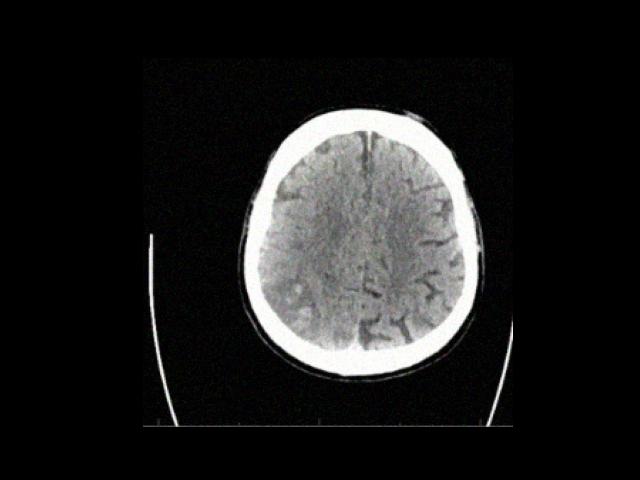

Sample Gallery